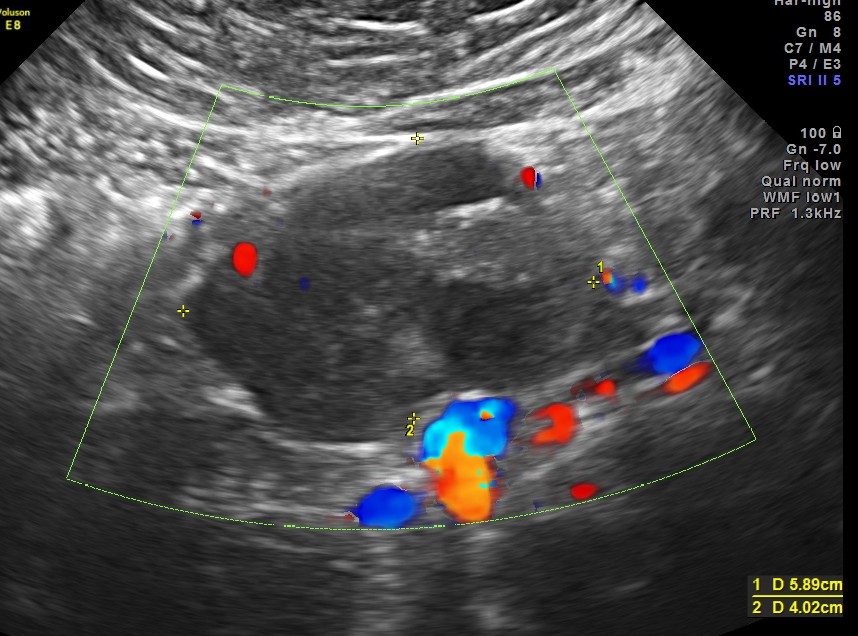

Now for the unexpected findings . To finish off the scan , I was sweeping the aorta, IVC and the pre and post aortic regions.

The following image was obtained with the transducer in the mid epigastric region and an inch to the left of the mid line.

This mass visualised there . This was antero-lateral to the aorta and showed mixed echotexture , with some vascularity.

This was not mobile and all i could offer was a description of what was seen with the impression of a mass of unknown origin – ?? enlarged node and advised further work up.